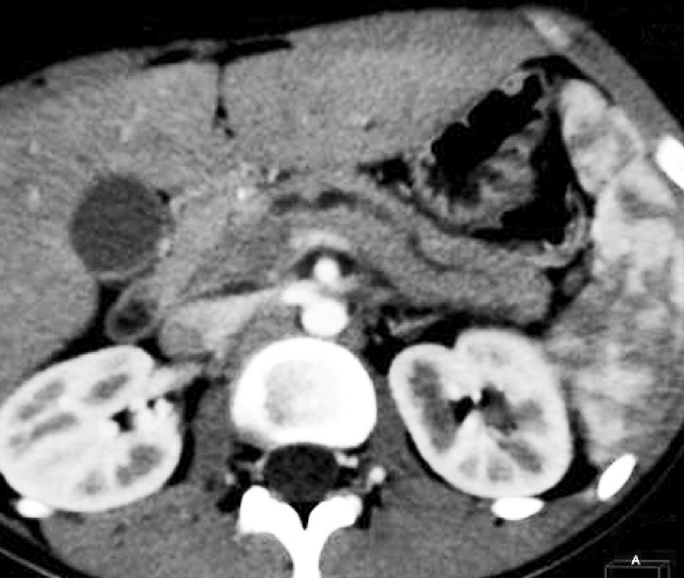

МСКТ: в проекции головки ПЖ прослеживается округлое патологическое образование с нечеткими, неровными контурами, окруженное сосудами, размерами 30 × 40 × 60 мм. Мезентериальные и парааортальные лимфатические узлы не увеличены.

КТ (контроль): при сопоставлении с данными предыдущей МСКТ положительная динамика — уменьшилась степень расширения вирсунгова протока до ~3 мм (ранее ~5 мм). Отмечается также уменьшение размеров ПЖ в области тела и хвоста (13 × 15 мм соответственно). Перестали прослеживаться инфильтрация в парапанкреатической клетчатке и скопление жидкости в этой области. Сохраняется увеличение головки ПЖ до 30 × 40 мм (нельзя исключить уменьшения на 1–2 мм). Структура ее неоднородная, с более плотными участками (до 45 HU в сравнении с остальными отделами 40 HU).

Контуры железы мелкофестончатые. Контрастирование своевременное, достаточно гомогенное, диаметром до 14 мм.

Заключение: КТ-картина увеличения размеров и неоднородности структуры ПЖ в области головки. Положительная динамика в сравнении с данными предыдущей МСКТ (рис. 4).